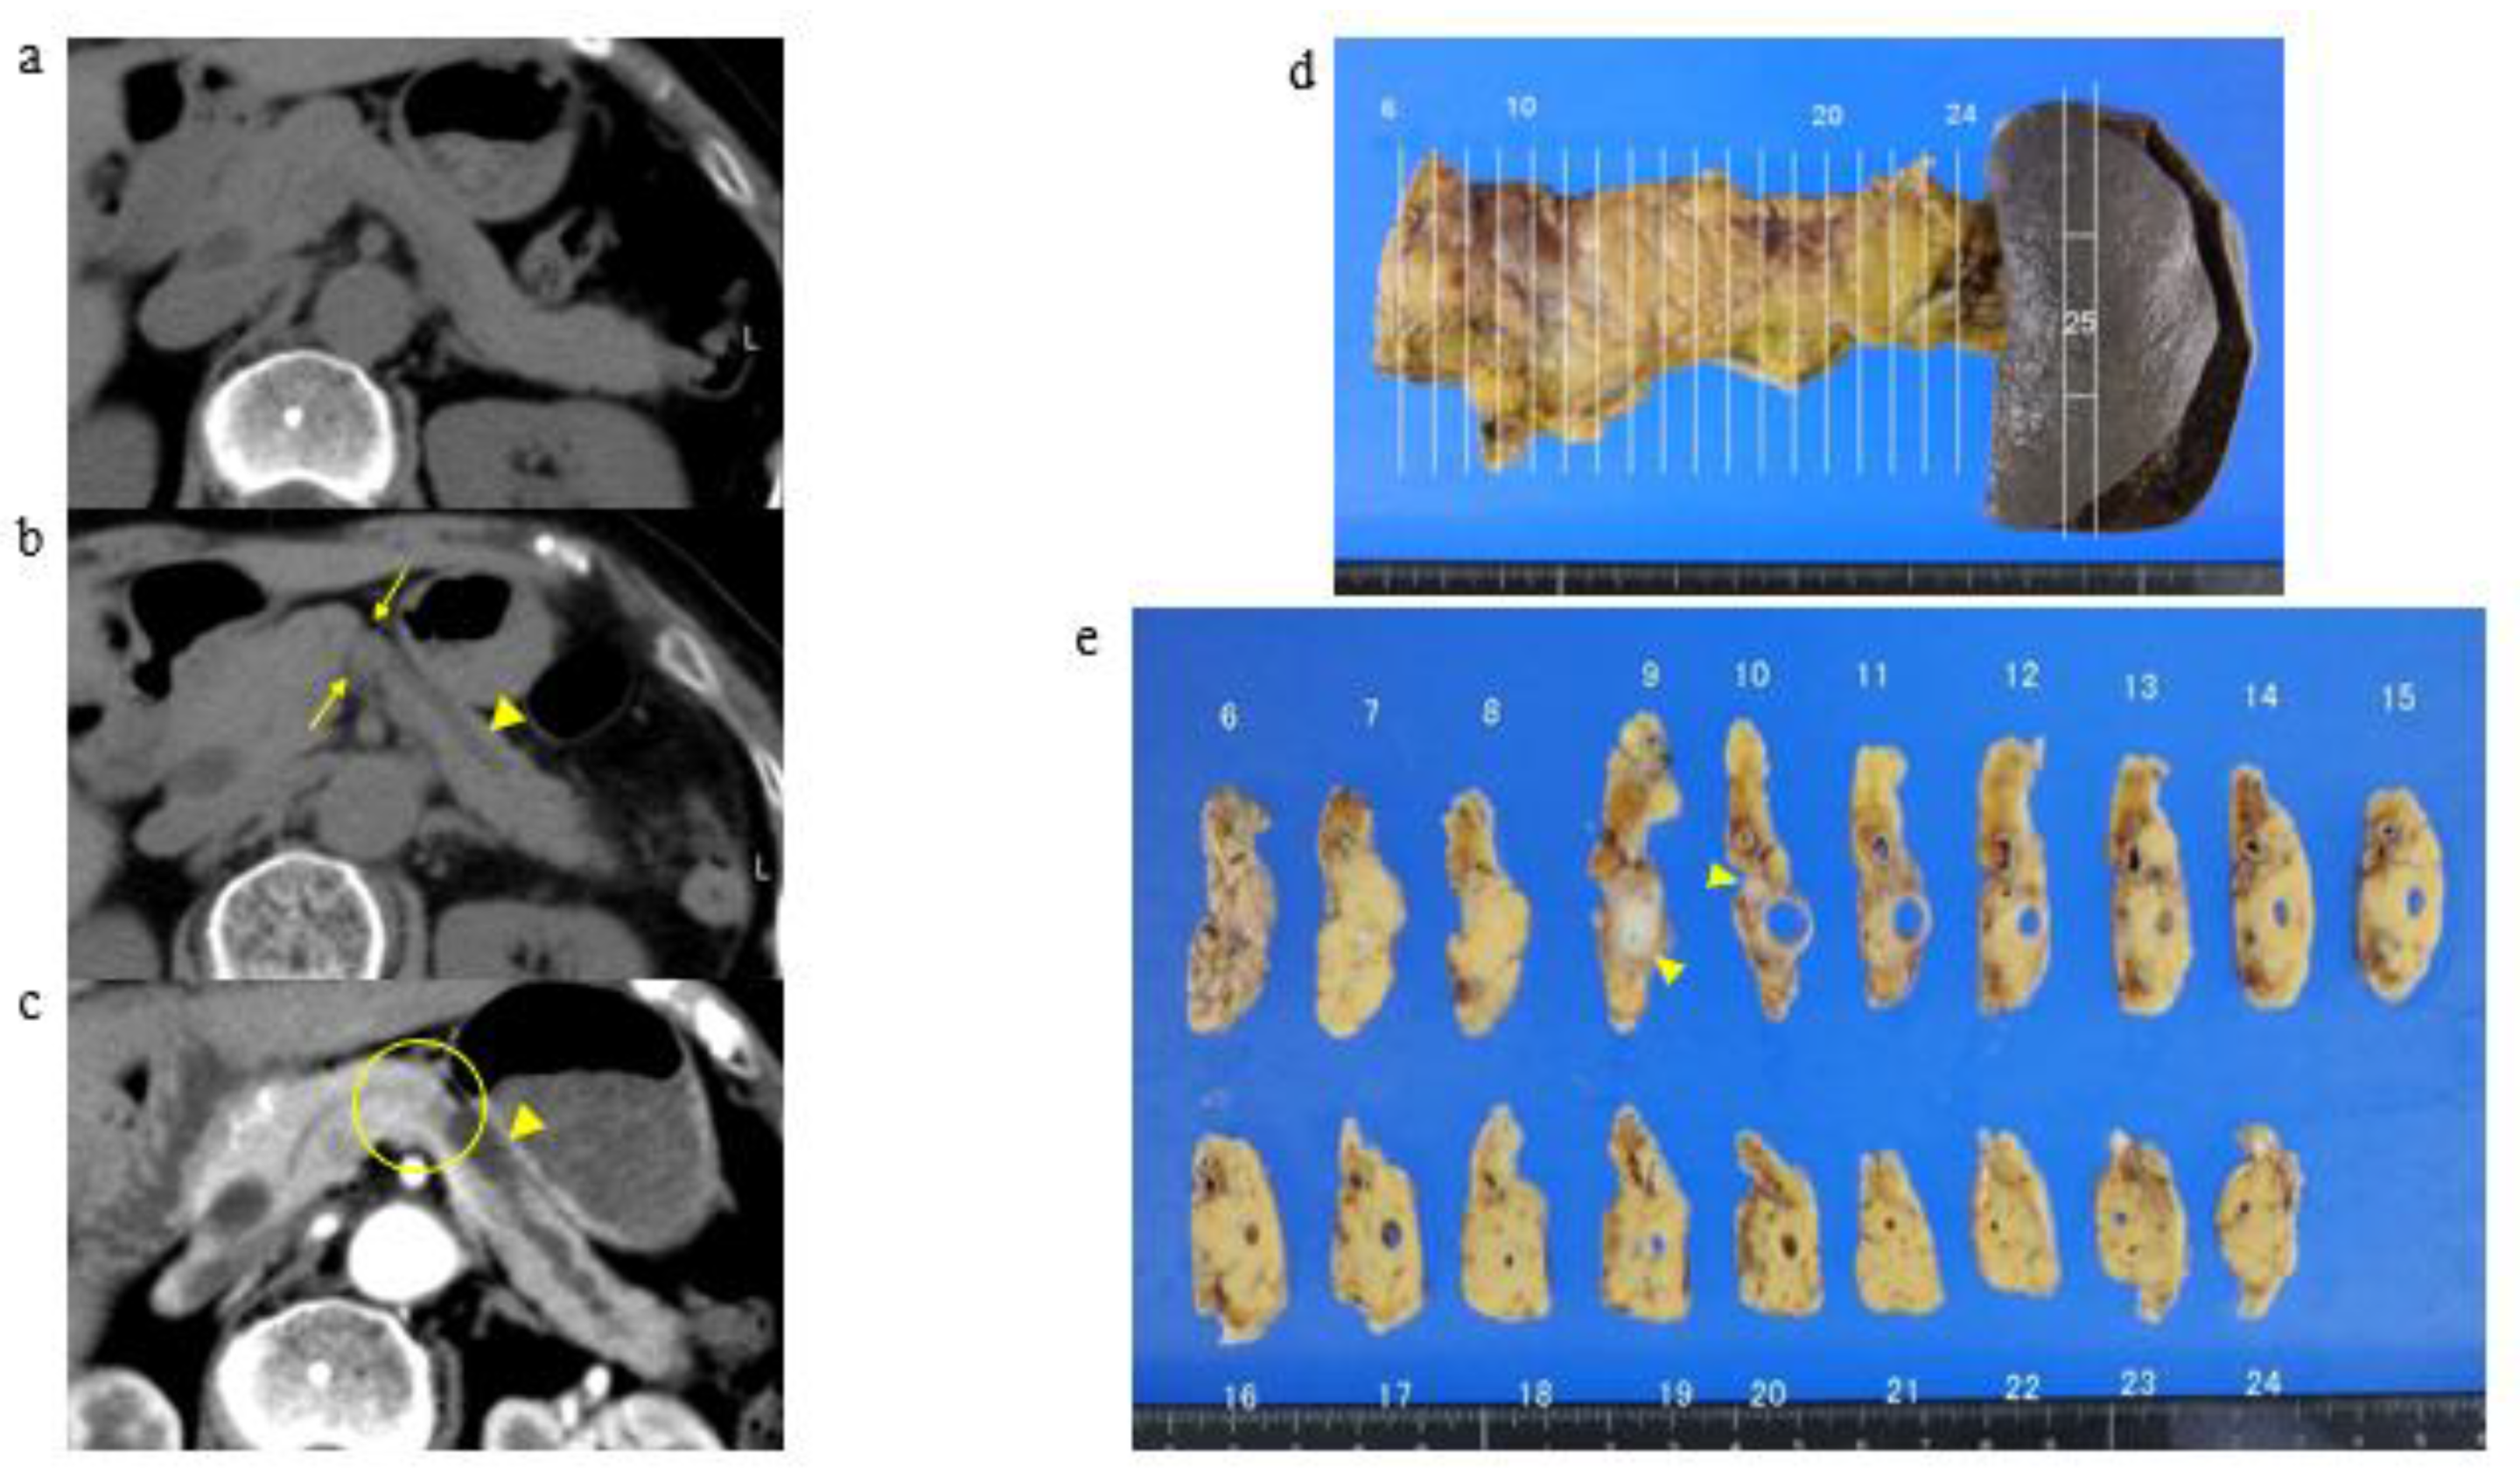

3.2. A Representative Case and Classification by Specific Abnormality of the Pancreas

3.3. Time to Development of Pancreatic Cancer